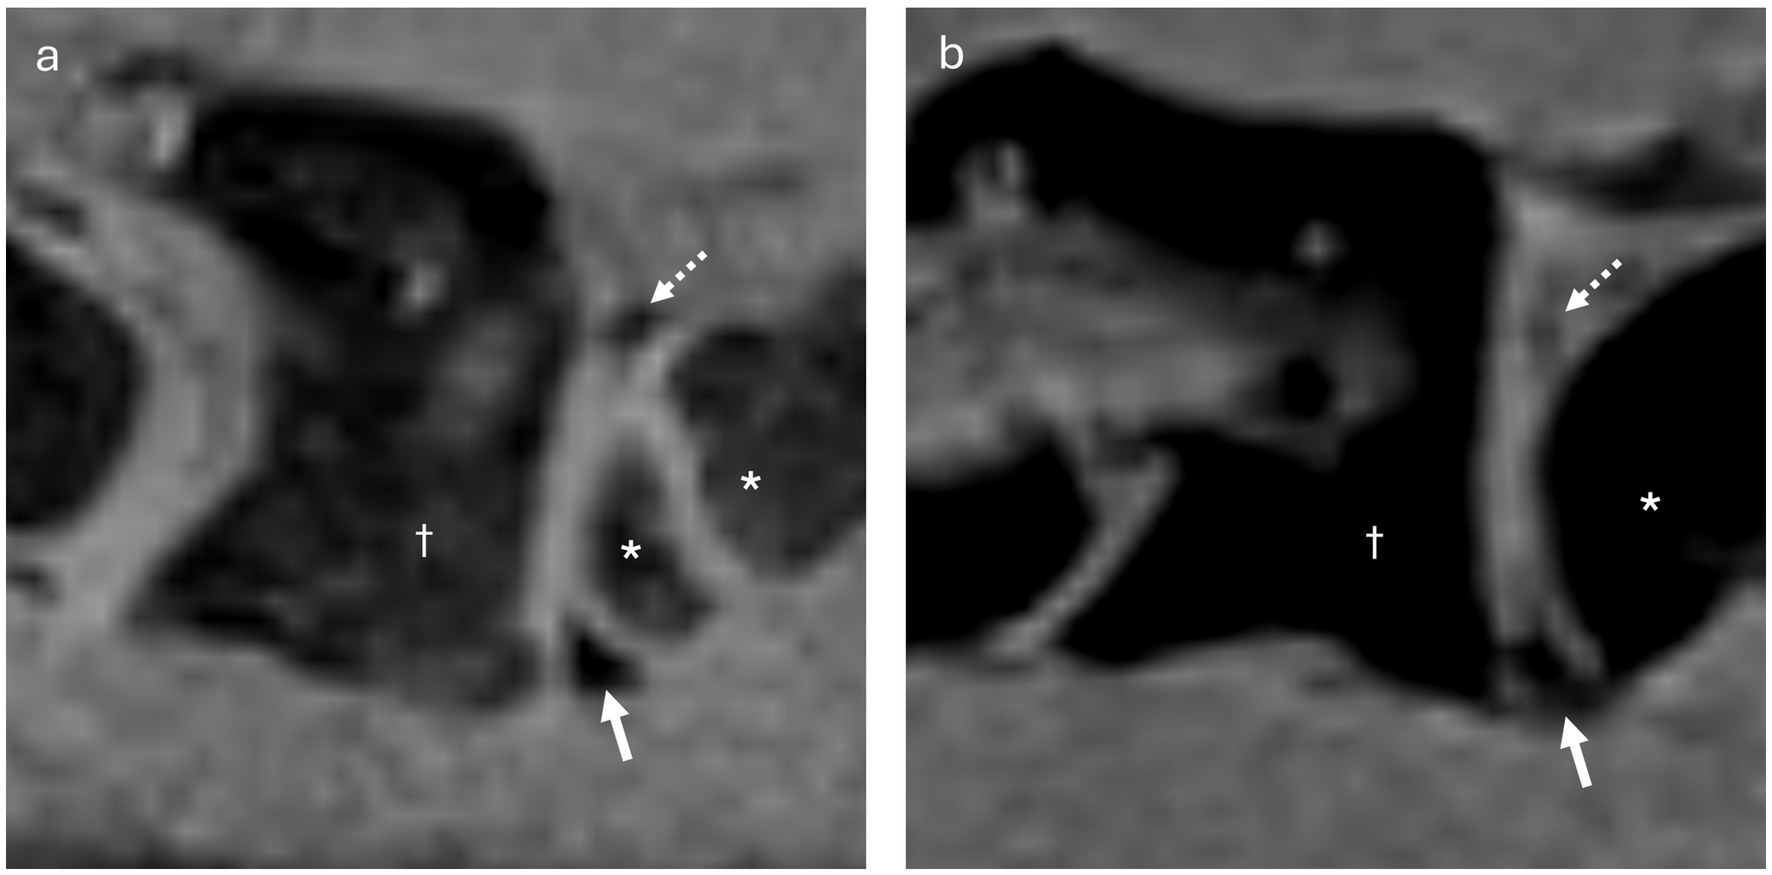

Purpose Synovial folds of the lateral atlantoaxial joints are well described normal anatomical structures in humans, which play a potential role in neck pain; however, scant information exists regarding these structures in dogs. The purpose of this study was to identify and describe atlantoaxial synovial folds in dogs using magnetic resonance imaging (MRI), gross anatomy and histological examination. Methods Six client-owned dogs, euthanized for reasons unrelated to this study and without known disease in the craniocervical region, underwent postmortem MRI of the cranial cervical spine (3 Tesla, Siemens Magnetom Vida) using T2-weighted (T2w), T1-weighted (T1w), short tau inversion recovery (STIR), Dixon, and fat-suppressed volumetric interpolated breath-hold examination (VIBE) sequences. In five dogs the lateral atlantoaxial joints were gross anatomically dissected, while one of them underwent histological examination. Results Fat-suppressed VIBE sequences provided optimal visualization of synovial folds within the atlantoaxial joints. Ventral synovial folds were discernible in all dogs by MRI and gross anatomical examination presenting as ventral synovial bulges extending into the joint space. While smaller dorsal synovial folds were identified by MRI only in 2 dogs, but by gross anatomical examination in all dogs. Light microscopy of the histological specimen confirmed that the folds were extensions of the joint capsule`s synovial membrane, which were mainly composed of vascularized connective and adipose tissue; and were covered by synovial cells. Discussion/Conclusion Synovial folds are present in canine atlantoaxial joints free from known atlantoaxial disease. Dorsal and ventral folds could be visualized on post-mortem macroscopic and histological examinations. The larger ventral folds were consistently visualized using MRI with fat-suppressed VIBE sequences. The anatomical structure of the canine synovial folds suggests a similarity to humans, indicating that some conditions may analogously affect the synovial folds. Further investigations are warranted to elucidate the clinical relevance of these synovial folds in dogs.